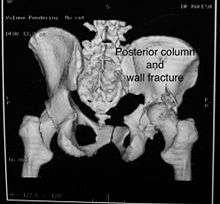

Posterior column with posterior wall / Transverse with posterior wall Fractures

These fractures are extension of elementary fractures. With involvement of posterior wall, the difficulty in treatment increases. These fractures are rarely amenable to non-surgical treatment. Due to posterior wall fracture, the hip is usually dislocated posteriorly, requiring immediate reduction of dislocation and surgical reconstruction after few days.

Cause: Posterior column with posterior wall fracture occurs due to dash board injury, while transverse fracture with posterior wall fracture occurs due to combined dash board injury and direct injury to the hip from the side.

Associated injury: to the sciatic nerve may occur

How to diagnose: Antero posterior view may give clue to these injuries, Judet views and CT scan help in knowing the extent of injury

Combined both column fractures

These are the most complex injuries. Here the weight bearing roof or dome of the acetabulum is a floating piece. This adds to complexity of management.

Cause: Combination of forces acting on the hip though the femoral head

Associated injury: Sciatic nerve, may be femoral nerve or vessels

How to diagnose: all three x-ray views plus CT scan is a must for diagnosis and management of this complex injury